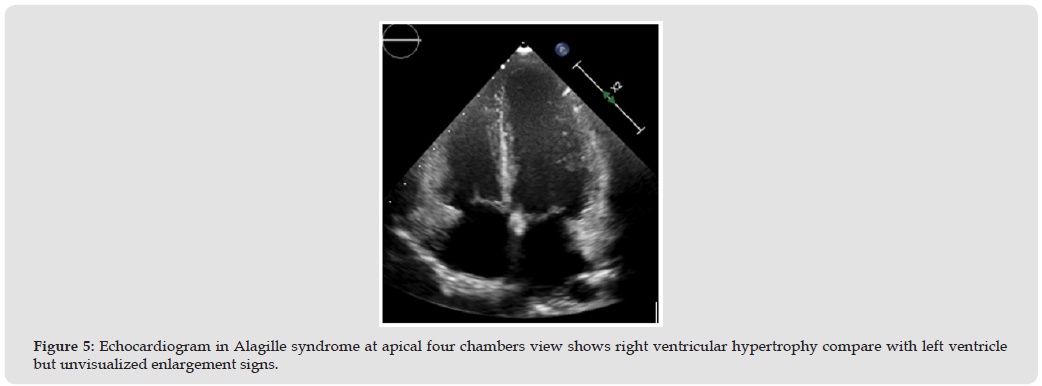

Alagille syndrome have main condition associate with cardiac are right side heart obstruction such as peripheral pulmonary artery stenosis (PPS). PPS was a common problem and cause for check echocardiography, lead to right heart hypertrophy or pressure elevated and relate to cyanotic signs in some case [7] (Figure 5) The remodeling of vascular intima, tunica media and adventitia lead to not progression of pulmonary artery branches size [8] In normal population, the echocardiography uses McGoon ratio for assessing PA size compare with abdominal descending aorta [9] If McGoon ratio = RPA+LPA/DAo has a value greater than 1.5 or 2.0 indicate to good size of the pulmonary artery [10] If z-score less than -2 may be considering pulmonary artery size abnormal or small, and need to measure pressure gradients across of dual branches, main pulmonary artery, and annulus valve of pulmonic if greater than 60 mm Hg May be considered severe stenosis [11,12] (Figure 6) However, the parasternal short axis of aortic valve level view focusing MPA, PV, and PA branches was a necessary view of measure size and PG across due to the direction of blood flow parallel the echo beam. In the children have a suprasternal long and short axis view is necessary window identified pulmonary artery structure, confluence appearance and size. Especially if we keep transducer marker to the left of the patient about 3 o’clock direction posterior angulation, this view able to visuals the first-loba branches of RPA too. (Figures 7 & 8).